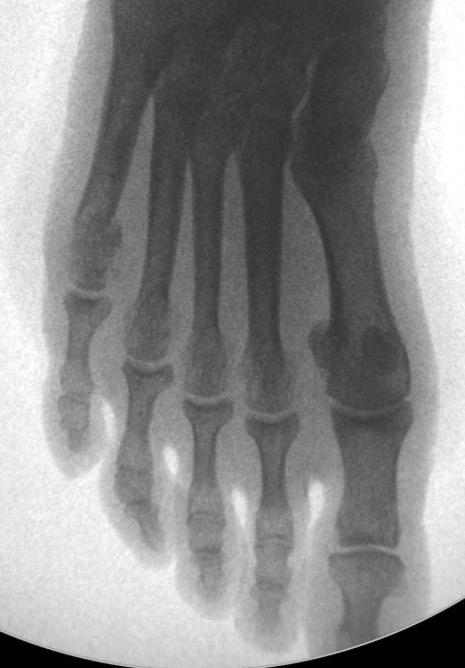

LE SYNDROME DU DEUXIEME RAYON EST SOUVENT LA CONSEQUENCE INELUCTABLE d'un

hallux valgus négligé...

Le patient se plaint de douleurs plantaires (métatarsagies) mais aussi dorsales. L'orteil apparait en griffe et il se produit peu à peu une luxation métatarso-phalangienne dorsale (le deuxième orteil est spontanément relevé par rapport aux autres, voire complètement luxé lorsque se rompt la plaque plantaire, renforcement qui stabilise l'articulation).

Il est parfois isolé.